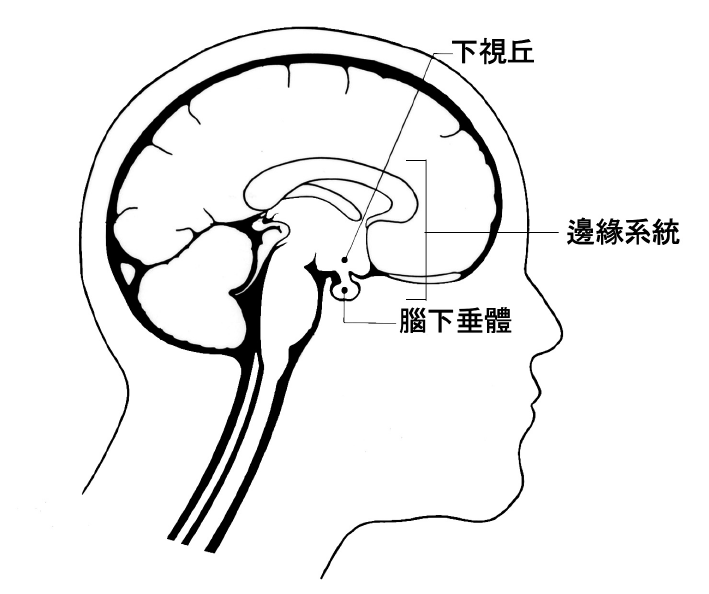

在第二篇的第三章談夢和情緒時,我已經提過「情緒腦」,也就是邊緣系統(limbic system)——位在中腦和大腦之間邊緣地帶的腦部組織。情緒腦,是大腦接收資訊的過濾網。它既影響情緒,為認知加上一層情緒的色彩,而讓我們不可能客觀。

在情緒腦,有一個部位叫做下視丘(hypothalamus)。下視丘作為神經系統和內分泌之間的橋梁,影響腦下垂體這個內分泌的中樞,而進一步影響全身的內分泌。同時,也進一步調控交感神經和副交感神經的作用。

假如你還記得,我們的日週期是跟著太陽走,才有一個接近24小時的日週期,而依照白天和晚上的差別,有不同的生理的反應和運作。幾十年前,沒有人想過,那麼複雜的週轉,是由腦部的單一部位在控制,而這個部位在情緒腦裡。

就在下視丘裡,有一個視交叉上核(suprachiasmatic nucleus, SCN)在控制日週期。如果你還記得,解剖學家會稱之為「核」的腦部組織,指的就是神經細胞特別密集的地方。